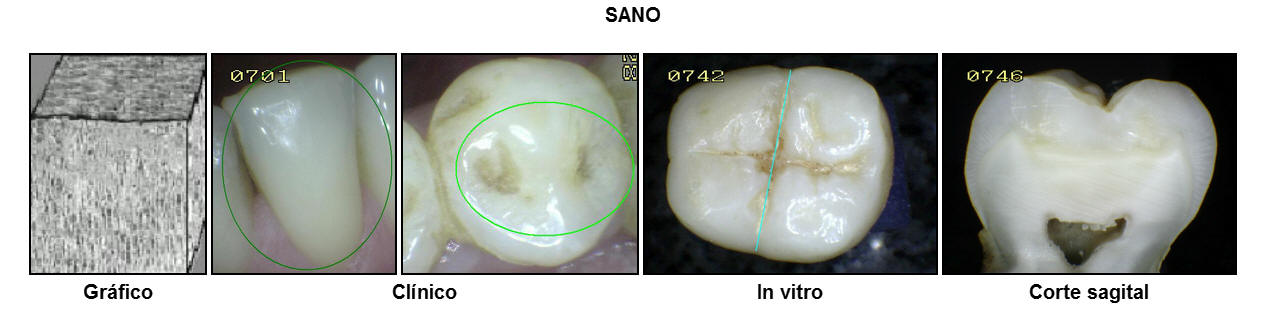

En el gráfico se muestra el

esmalte intacto en la superficie y la sub-superficie. El

aspecto clínico del esmalte es brilloso y translúcido al

secado con aire durante 5 segundos. Se puede observar

pigmentaciones extrínsecas, no consistentes con

desmineralización.